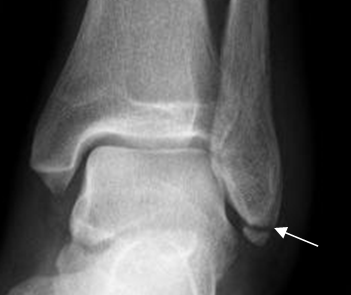

Fig 42. Fractura del maléolo externo.

Rx AP. Fractura del maléolo externo, por debajo de la sindesmosis.